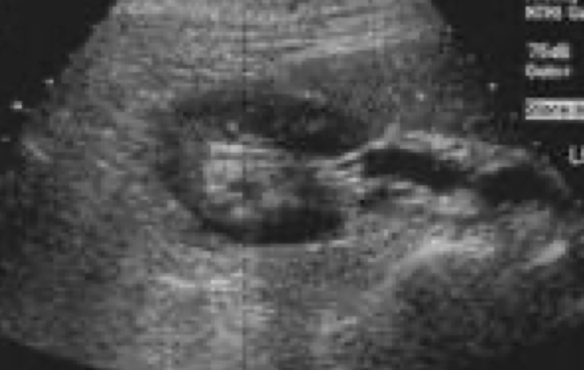

What portion of the kidney is this that looks like a donut

upper & lower poles in transverse